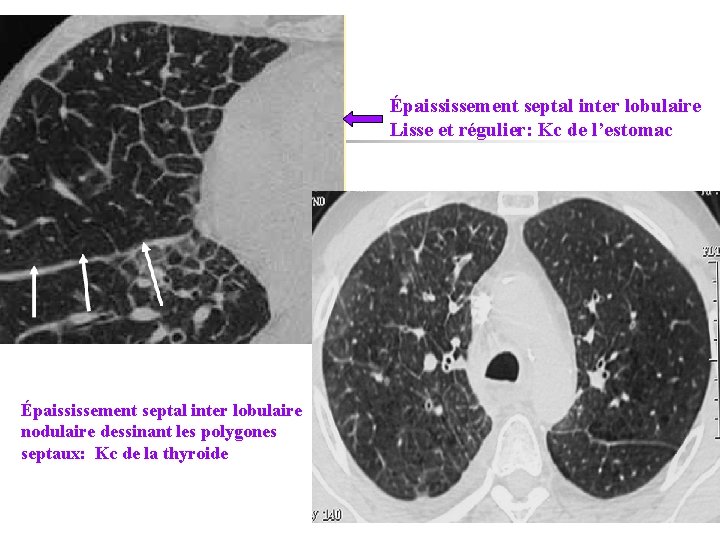

Épaississement septal inter lobulaire Lisse et régulier: Kc de l’estomac Épaississement septal inter lobulaire nodulaire dessinant les polygones septaux: Kc de la thyroide

Epaississement régulier Epaississement irrégulier , nodulaire: